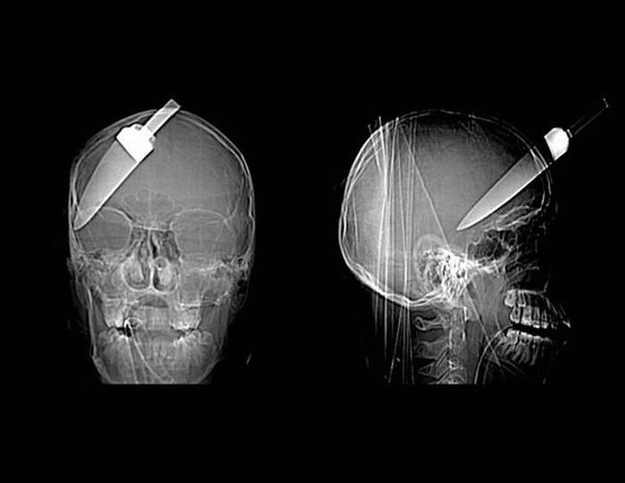

A 5-inch knife embedded in the skull of a teenage boy.